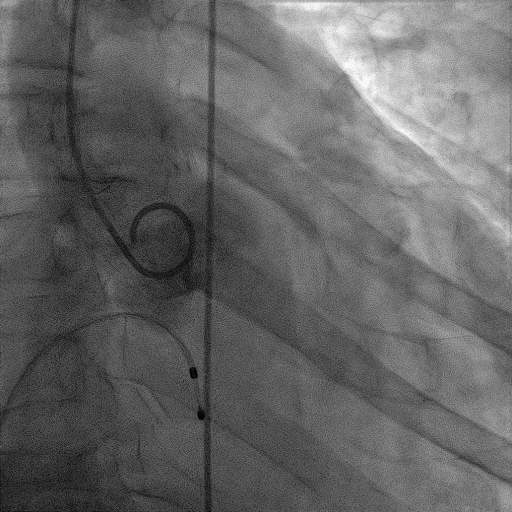

手术过程:

麻醉方式为全麻,建立静脉通路后,穿刺右侧股静脉,预埋ProGlide缝合器,食道超声指导下房间隔穿刺成功,鞘管扩张穿刺部位,沿导丝将导引导管送入左房,MitraClip调整后顺利到达二尖瓣目标位置,在X线及食道超声辅助下,将MitraClip NTR二尖瓣夹精确定位后,成功夹合二尖瓣A2-P2区,超声显示反流明显减少,多切面证实夹合组织充分,肺静脉多普勒波形由反向恢复正常,手术顺利结束,安返普通病房。

术中超声引导:

确定房间隔穿刺点:靠后

穿刺点高度测量:4.14cm

2D视图下测量大鞘长度2.2cm

2D视图下建立trajectory

3D视图打开夹子

3D视图下调Rotate,定位2区

X-plane:下夹子尝试捕获2区

夹子逐渐夹闭后,2区返流逐渐减少

3D:测量前叶长21.2mm,后叶长10.2mm

X-plane:计算前叶捕获长度6.8mm,后叶捕获长度6.5mm

夹子放置后二尖瓣口平均跨瓣压差:3mmHg

肺静脉血流频谱恢复正常

3D视图下观察二尖瓣双孔形态

3D-color:残余少量返流